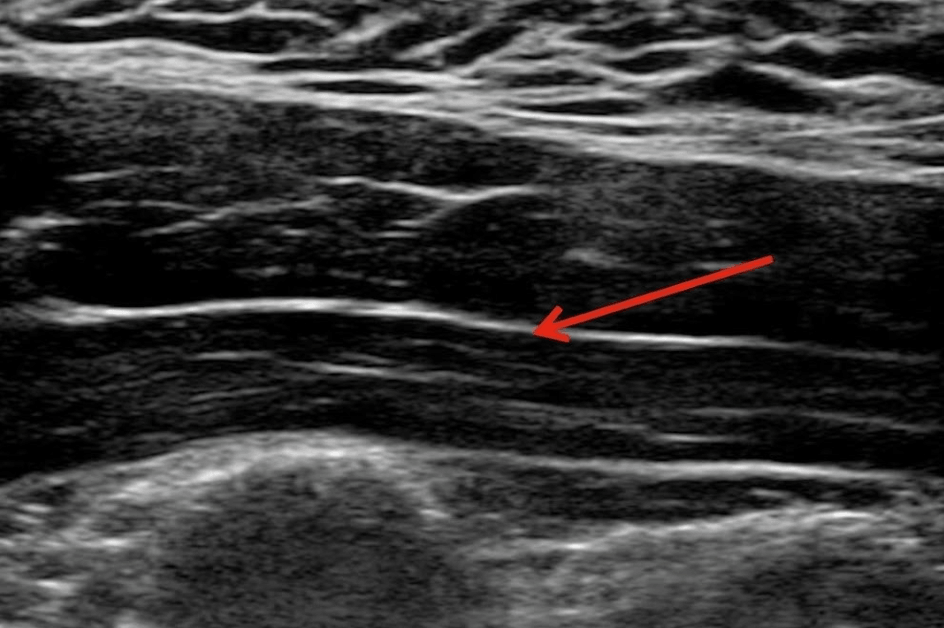

医師の手探りではなく、最新の超音波エコー装置を使って、皮膚の下の「筋膜が白く癒着している部分(痛みの原因)」をミリ単位で正確に見つけ出します。

1)筋膜の癒着で血行の悪くなった筋繊維がコリや痛みの原因となります。2,3)注射で癒着を剥離すると、直ちに症状が改善することが多いです。